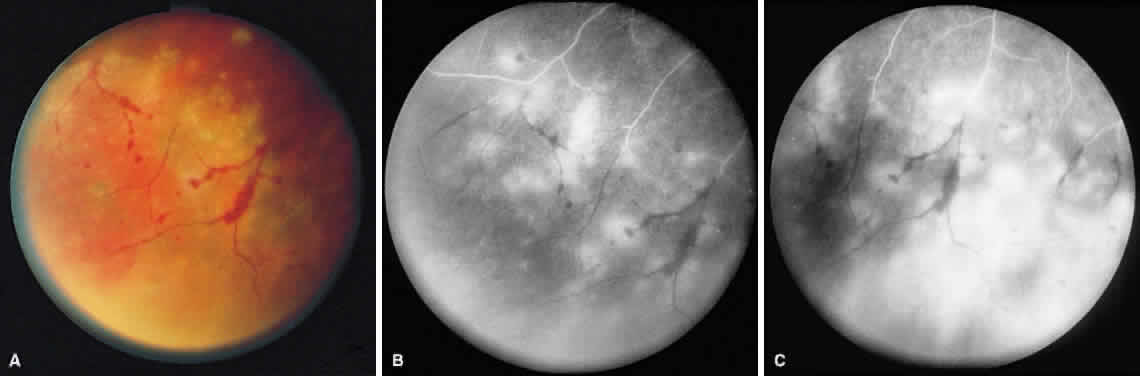

ARN is characterized by a retinal vasculitis affecting both the arteries and veins in the fundus, which is manifested by sheathing of the larger vessels (Fig. 2).7–10,16 Initially, patchy areas of peripheral retinal whitening (“thumbprint lesions”) representing full-thickness retinal necrosis are present or develop shortly after the vasculitis (Fig. 3). During a course that may span days or weeks, these patches coalesce into geographic areas (Fig. 4A). The entire peripheral retina (360 degrees) may be involved, or, more commonly, there are several noncontiguous patches of necrosis, each covering from a half to three clock hours (Figs. 5 and 6). The posterior segment lesions may not be detected without examination of the peripheral retina.

Fig. 4. A. With progression of ARN, the areas of retinal whitening begin to coalesce. Mild perivascular retinal hemorrhages are noted. B. Fluorescein angiography in the venous phase reveals retinal vascular nonperfusion in areas of active retinitis. C. In the late-phase angiogram, fluorescein hyperfluorescence is seen in areas of retinitis and around the retinal vasculature.

As the infection progresses, the leading edge of confluent retinal whitening advances toward the posterior pole (Fig. 7A). The retinitis may not progress posteriorly to the vascular arcades, sparing the macula and central vision. It is hypothesized that the retinal necrosis in ARN results from the combined effect of intracellular viral replication with subsequent cell death and vascular occlusion secondary to acute vasculitis. In some patients, the retinal vasculitic component may be much more prominent than the retinal necrosis.7 Optic disc swelling, either hyperemic or pallid, is a common feature of the ARN syndrome.1 Perivascular hemorrhages may be present (Fig. 8); however, widespread areas of retinal hemorrhage are atypical. Retinal vascular occlusion, often involving the arteries, can occur at any point during the clinical course. Without treatment, the inflammatory component of ARN typically burns out in 6 to 12 weeks, leaving behind a thin atrophic retina with associated pigmentary changes.10

Fig. 7. A. Active ARN with diffuse retinal necrosis progressing into the macula and areas of retinal hemorrhage. The hazy view is secondary to vitreous inflammation. B. Fluorescein angiogram in the venous phase of active ARN syndrome in this eye reveals peripheral vascular nonperfusion, as well as optic nerve and perivascular hyperfluorescence.

Intravenous fluorescein angiography may be helpful in delineating the extent of infection and elucidating the cause of central visual loss. In the early frames, choroidal perfusion defects may be seen; these defects are caused by areas of focal choroidal inflammatory cell accumulation and overlying retinal pigment epithelial damage (Fig. 16). Such choroidal perfusion defects may occur away from zones of active necrosis.42 Acute obstruction of the central retinal artery or any of its branches may be present. Peripheral views in the areas of active retinitis commonly show little or no intravascular fluorescein in the retinal arteries and veins. Often an abrupt “cut-off” of the intravascular fluorescein may be apparent at the edges of the retinal inflammation (see Fig. 4B and C). Areas of active retinitis show blockage of the underlying choroidal fluorescein pattern (see Fig. 7B). Recirculation phase views may reveal macular leakage, optic disc, and retinal vasculature staining.